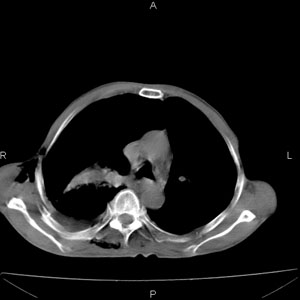

患者男,77岁,于3日前从树上摔下,头部查ct示蛛血,硬膜下出血,上腹部ct未见明显异常,右侧胸腔积液,左侧如常。肺部拍片示右侧肋骨多发骨折住院后今日来查肺部ct,我看到的是1。右侧胸腔血气胸并右肺上叶,中叶压缩性肺不张,2。右肺下叶肺挫伤并多发肋骨骨折,肌内及皮下积气3。左侧少量胸腔积液,我想请教的是3天前左侧胸腔里没有积液今天怎么出现了呢,是什么原因呢?请讨论。

考虑外伤性迟发性胸腔积液。

右侧液气胸,胸膜创伤、肺组织挫伤,渗出属正常反应。